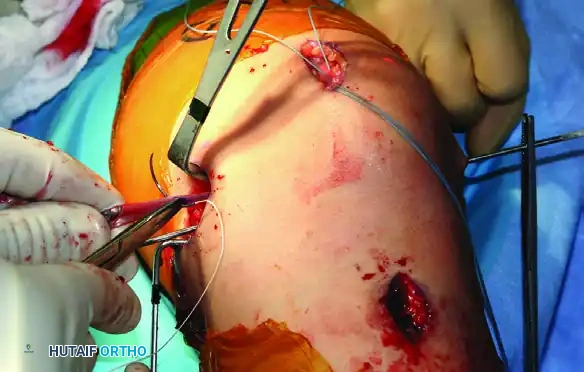

Graft Passage, Tensioning, and Fixation

- Patellar Fixation: Place the looped end of the graft into the patellar trough. Secure the graft to the patella using one set of paired sutures from each anchor. Preserve the second set of sutures for later retinacular repair.

- Graft Passage: Pass the whipstitched tails of the graft through the extrasynovial soft tissue tunnel to the femoral incision.

Figure 47-15D: Graft tails passed through the extrasynovial soft tissue tunnel toward the femoral footprint.

- Tensioning: Pull the graft taut into the femoral tunnel. Flex the knee to 30 degrees. Apply a lateral translation force to the patella. The graft should be tensioned to allow one to two quadrants of lateral passive glide.

- Femoral Fixation: Once physiological tension is determined, mark the graft at the tunnel aperture. Cut the excess graft 20 mm distal to this mark. Place absorbable whip sutures in the new tails, pass them through the eyelet of a Beath pin, and pull them out the lateral aspect of the thigh. Secure the graft in the femoral tunnel using a biocomposite interference screw that is 1 mm smaller than the tunnel diameter.